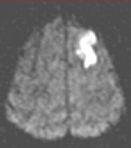

In the brain, it is used to determine hyperacute and acute strokes (detectable from minutes to days). Conventional imaging may not be able to detect hyperacute strokes or differentiate acute from chronic infarcts. With MR diffusion, detection of acute infarcts is immediate and differentiation from old infarcts is obvious.

Routine FLAIR MRI images (left) cannot differentiate between acute infarcts and chronic ischemic changes/infarcts. The diffusion MRI (right) clearly demonstrates an acute infarct in the left frontoparietal region (the chronic changes do not "light up" on the diffusion study).